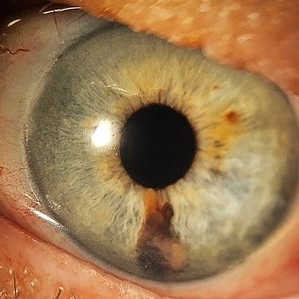

Iris Melanoma

Jul 11 2013 by Jason S. Calhoun

Iris melanoma.

Photographer: Jason S. Calhoun, Department of Ophthalmology, Mayo Clinic Jacksonville, Florida

Condition/keywords: iris melanoma